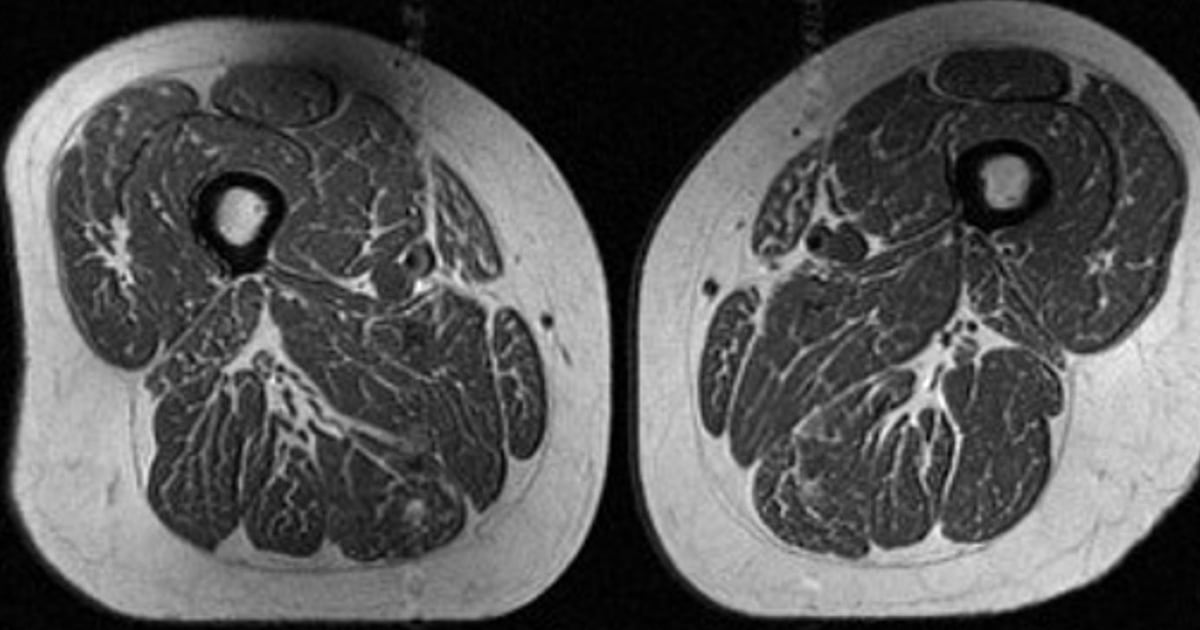

ونشر الأطباء صورة لمقطع عرضي لفخذ امرأة كانت تتلقى 87% من تغذيتها من الأطعمة فائقة المعالجة، مثل حبوب الإفطار السكرية، وألواح الشوكولاتة، والمشروبات الغازية. ورغم ممارستها نشاطا بدنيا معتدلا، ظهرت عضلات فخذها مليئة بالدهون المخططة الشبيهة باللحم المدهون.

وأظهرت صور الرنين المغناطيسي للمشاركين أن أكثر العضلات تضررا هي الفخذين الداخليين، ثم أوتار الركبة، بينما تأثرت العضلات الرباعية بنسبة أقل. وكانت النتائج متطابقة بين الرجال والنساء، وكان الارتباط أقوى عند قياس محيط الخصر بدلا من مؤشر كتلة الجسم.